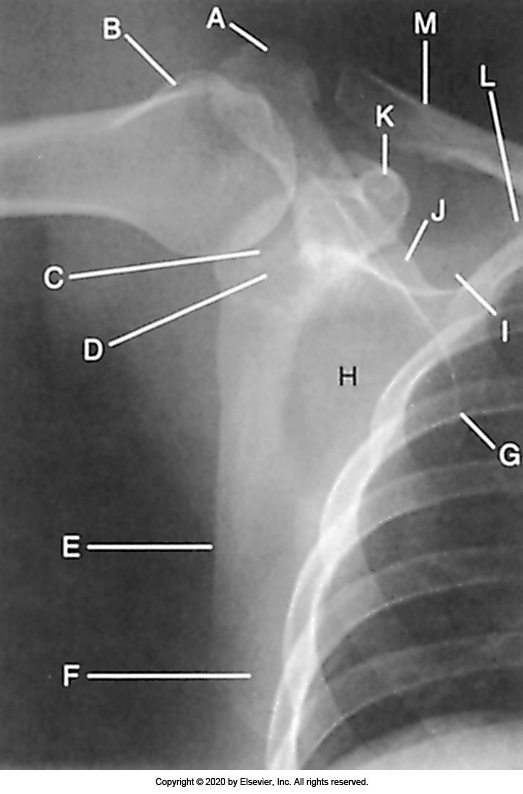

Identify the labeled "K" anatomy in the image below:

Radial head

Medial epicondyle

Lateral epicondyle

Olecranon

Identify the labeled "H" anatomy inn the image below:

Coronoid

Humerus

Capitulum

Identify the labeled "D" anatomy in the image below:

Greater tubercle

Identify the labeled "I" anatomy in the image below:

Coracoid process

Humeral head

Acromion process